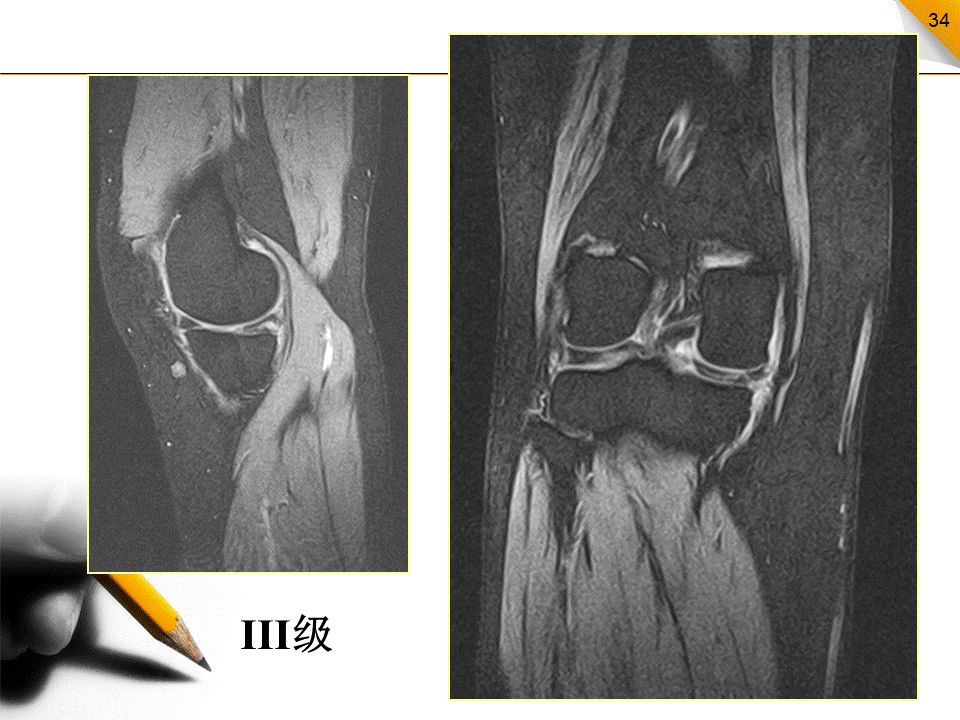

半月板损伤的MR分级

0级:正常半月板,均匀的低信号,形态规则I级:不与半月板关节面相接触的灶性信号增高影II级:半月板内线性信号增高,可延伸至半月板的关节囊缘,但未达到半月板的关节面缘,是I级信号改变的继续,范围更广III级:半月板内的高信号达到半月板的关节面,代表半月板的撕裂IV级:半月板破碎成多块并向关节腔内移位